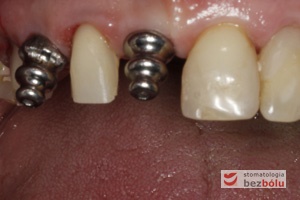

Ostateczne tytanowe filary protetyczne in situ - ofrezowane i przygotowane laboratoryjnie łączniki wprowadzone do implantów

Ostateczne tytanowe filary protetyczne in situ – ofrezowane i przygotowane laboratoryjnie łączniki wprowadzone do implantów